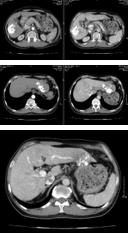

- Siêu âm ổ bụng: Khối u gan phải theo dõi thể thâm nhiễm

- CT scanner ngực-bụng: U gan phải tính chất HCC thể thâm nhiễm, kích thước ~ 58x80x77mm xâm lấn tĩnh mạch cửa (Vp2) - hạ phân thùy II có nốt giảm tỷ trọng ngấm thuốc kém đường kính 8mm. Lồng ngực hiện không phát hiện tổn thương nghi thứ phát.

• Chẩn đoán xác định: UTBMTBG giai đoạn BCLC C – Xơ gan child A - VGB

• Phương pháp điều trị: Dùng thuốc đích Lenvatinib 8mg/ngày + thuốc kháng virus Tenofovir 300mg/ngày

• Đánh giá đáp ứng:

| Trước điều trị | Sau 1 tháng | Sau 2 tháng |

| Hình 8. Khối u gan phải thể thâm nhiễm, xâm lấn tĩnh mạch cửa | | Hình 9. Khối u gan phải co nhỏ kích thước 54x67mm ranh giới rõ, còn tăng sinh mạch ít – Không còn nốt gan trái |

| AFP: 289,4ng/mL AFP-L3: 42% Pivka-II: 5382mAU/mL | AFP: 112,6ng/mL AFP-L3: 40% Pivka-II: 2756mAU/mL | AFP: 66,0ng/mL AFP-L3: 31,3% Pivka-II: 1109mAU/mL |

Bảng 4. Đánh giá đáp ứng điều trị bằng Lenvatinib

• Điều trị tiếp theo: Điều trị Lenvatinib kết hợp nút mạch. Sau 1 tháng đạt được đáp ứng hoàn theo tiêu chí mRECIST -> người bệnh được điều trị tiếp bằng phẫu thuật cắt gan.

| Lenvatinib + TACE | Trước phẫu thuật | Sau phẫu thuật |

| Hình 10. TACE u gan | Hình 11. Khối u gan phải co nhỏ ranh giới rõ, không tăng sinh mạch – Không còn nốt gan trái | Hình 12. Ổ tụ dịch vết mổ - Nhu mô gan còn lại không thấy khối nốt bất thường |

| AFP: 66,0ng/mL AFP-L3: 31,3% Pivka-II: 1109mAU/mL | AFP: 49ng/mL AFP-L3: 28% Pivka-II: 533mAU/mL | AFP: 7,37ng/mL |

Bảng 5. Đánh giá đáp ứng điều trị sau phẫu thuật

• Đánh giá đáp ứng: Bệnh đáp ứng hoàn toàn